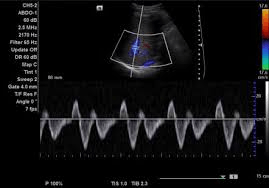

The splenic artery supplies the spleen, pancreas and the left side of the greater curvature of the stomach.These veins have hepatofugal flow direction and yield a W-shaped waveform as a result of changes in central venous pressure, respiration and compliance of the liver parenchyma.

The hepatic veins

Hepatofugal means flow AWAY from the liver.